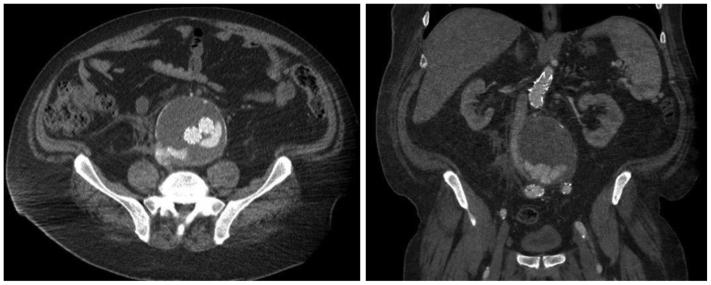

A primary aortocaval fistula (ACF) is a rare complication of abdominal aortic aneurysms caused by erosion of the aortic wall into the vena cava. It is more frequently observed in the setting of ruptured abdominal aortic aneurysms and presents a unique challenge for vascular surgeons. Both open and endovascular techniques exist, with the main differences being perioperative mortality and recurrence rates. We present a case of an ACF diagnosed intraoperatively, which persisted after endovascular aneurysm repair in conjunction with a type II endoleak. We applied a unique staged, triple endovascular approach to close the ACF via caval and aortic exclusion of inflow and outflow vessels.

原发性主动脉腔静脉瘘(ACF)是腹主动脉瘤的一种罕见并发症,由主动脉壁侵蚀进入腔静脉所致。在破裂性腹主动脉瘤中更常观察到,对血管外科医生构成独特挑战。开放手术和血管内技术都存在,主要区别在于围手术期死亡率和复发率。我们报告一例术中诊断为ACF的病例,该病例在血管内动脉瘤修复术后伴有II型内漏持续存在。我们采用了一种独特的分期、三重血管内方法,通过腔静脉和主动脉对流入和流出血管的封堵来闭合ACF。